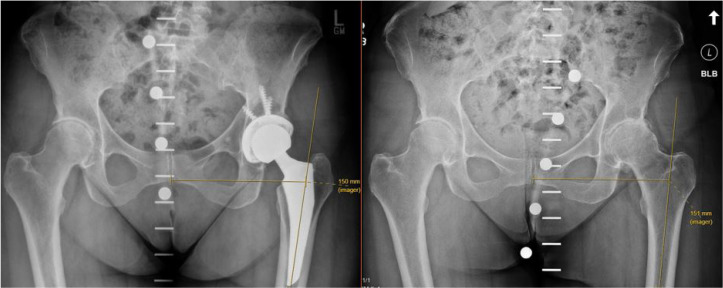

Materials and methods: Four hundred and ninety-nine THA patients at a single tertiary academic institution were retrospectively reviewed. Preoperative hip offset was measured on anteroposterior radiographs of the pelvis on the operative and contralateral side. Hip offset was also measured postoperatively on the operative side. Hip offset was measured using the Sundsvall method as the distance between the femoral axis and midline of the pelvis at the height of the lateral most point of the greater trochanter. All measurements were completed by two raters. Intra-class correlation coefficients (ICC) and Pearson's correlation coefficients were used to evaluate agreement and inter-observer reliability between two raters.

Abstract Image